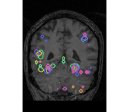

face

vs house

TV-l1

Graph-net

Social sparsity

Experiments outline a tradeoff between prediction accuracy and computation time. Fig. 1 displays the relative prediction accuracy and run time. TV- predicts best on average over the various classification tasks. However, it is followed closely by social sparsity which outperforms graph-net222All differences are significant in a Wilcoxon rank test.. The SVM performs much worse than the spatial sparsity, aside from the VBM data where we find that all models perform similarly.

Finally, an important aspect of the brain decoders is whether they segment well the brain regions that support the decoding. Such a question is hard to validate, yet there is evidence that TV- is a good approach [5]. Fig. 2 displays the decoder maps for the object-recognition tasks. For these tasks, we expect prediction to be driven by the functional areas of the visual cortex [27]. Indeed, the maps outline regions in known visual areas. The graph-net maps are much more scattered and less structured than the others. Conversely, the social sparsity maps are sparser and outline a smaller number of clusters.